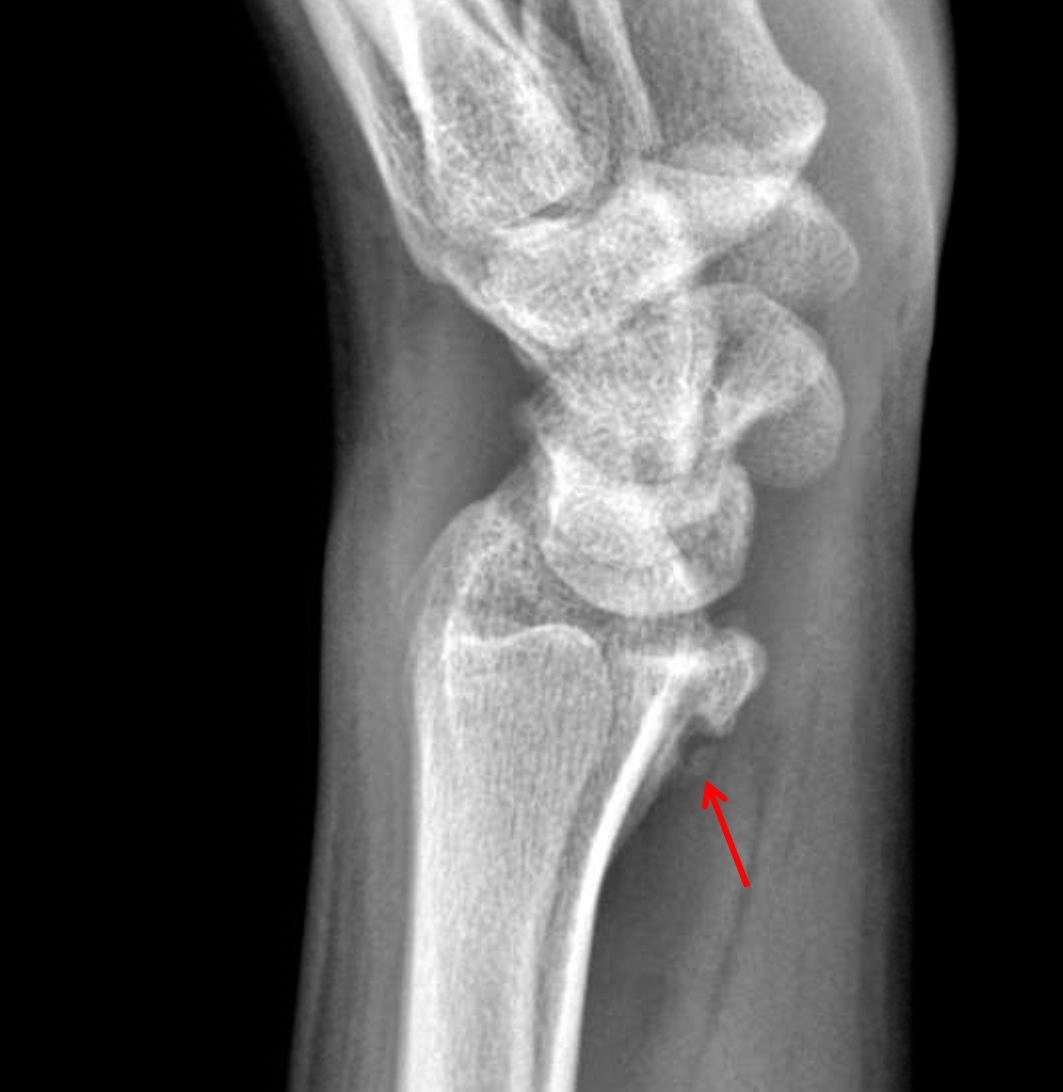

Characterized by an oblique fracture extending from the medial cortex implants for reverse obliquity fractures. Reverse obliquity and transverse fractures.

Combined femoral neck and shaft fractures: «another reverse obliquity intertrochanteric femur fracture for us! Subtrochanteric fracture repaired with cephalomedullary nail. The reverse obliquity fracture of the proximal femur is a recognized distinct fracture pattern mechanically different from most intertrochanteric fractures. Click here to see the statistics on journal of the korean fracture society. Reverse obliquity intertrochanteric fractures are unstable with unique anatomical and mechanical characteristics. In reverse obliquity intertrochanter fracture, the fracture line either passes through the femoral calcar above the lesser trochanter or directly through the lesser trochanter, which destroys the integrity of the. In journal of the korean fracture society. Subtrochanteric or reverse obliquity fractures strong evidence supports using a cephalomedullary device for the treatment of patients with subtrochanteric or reverse obliquity. The unstable patterns include reverse obliquity fractures, transtrochanteric fractures, fractures with a large posteromedial fragment implying loss of the calcar buttress, and fractures with. Combined femoral neck and shaft fractures: 355 x 509 jpeg 64 кб. Characterized by an oblique fracture extending from the medial cortex implants for reverse obliquity fractures. How not to miss, techniques o. Long or short nails and technical t. Backgroundreverse obliquity fractures of the proximal femur have biomechanical characteristics distinct from other intertrochanteric fractures and high implant failure rate when treated with sliding. These fracture can be difficult…»